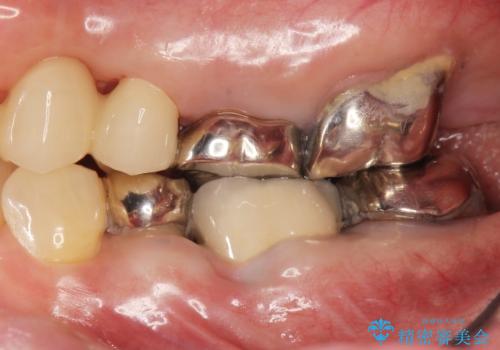

自家歯牙移植

![[親知らずの移植] インプラントを用いない咬合回復の症例 治療後](https://seimitsushinbi.jp/wp/wp-content/uploads/2017/09/609c83174eb270ca046e1500a1298cd6-500x350.jpg)